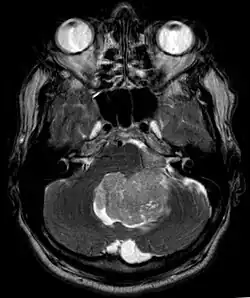

Ependymoma of 4.ventricle in MRI. -

Ependymoma of 4.ventricle in MRI. Left without, right with contrast-enhancement.